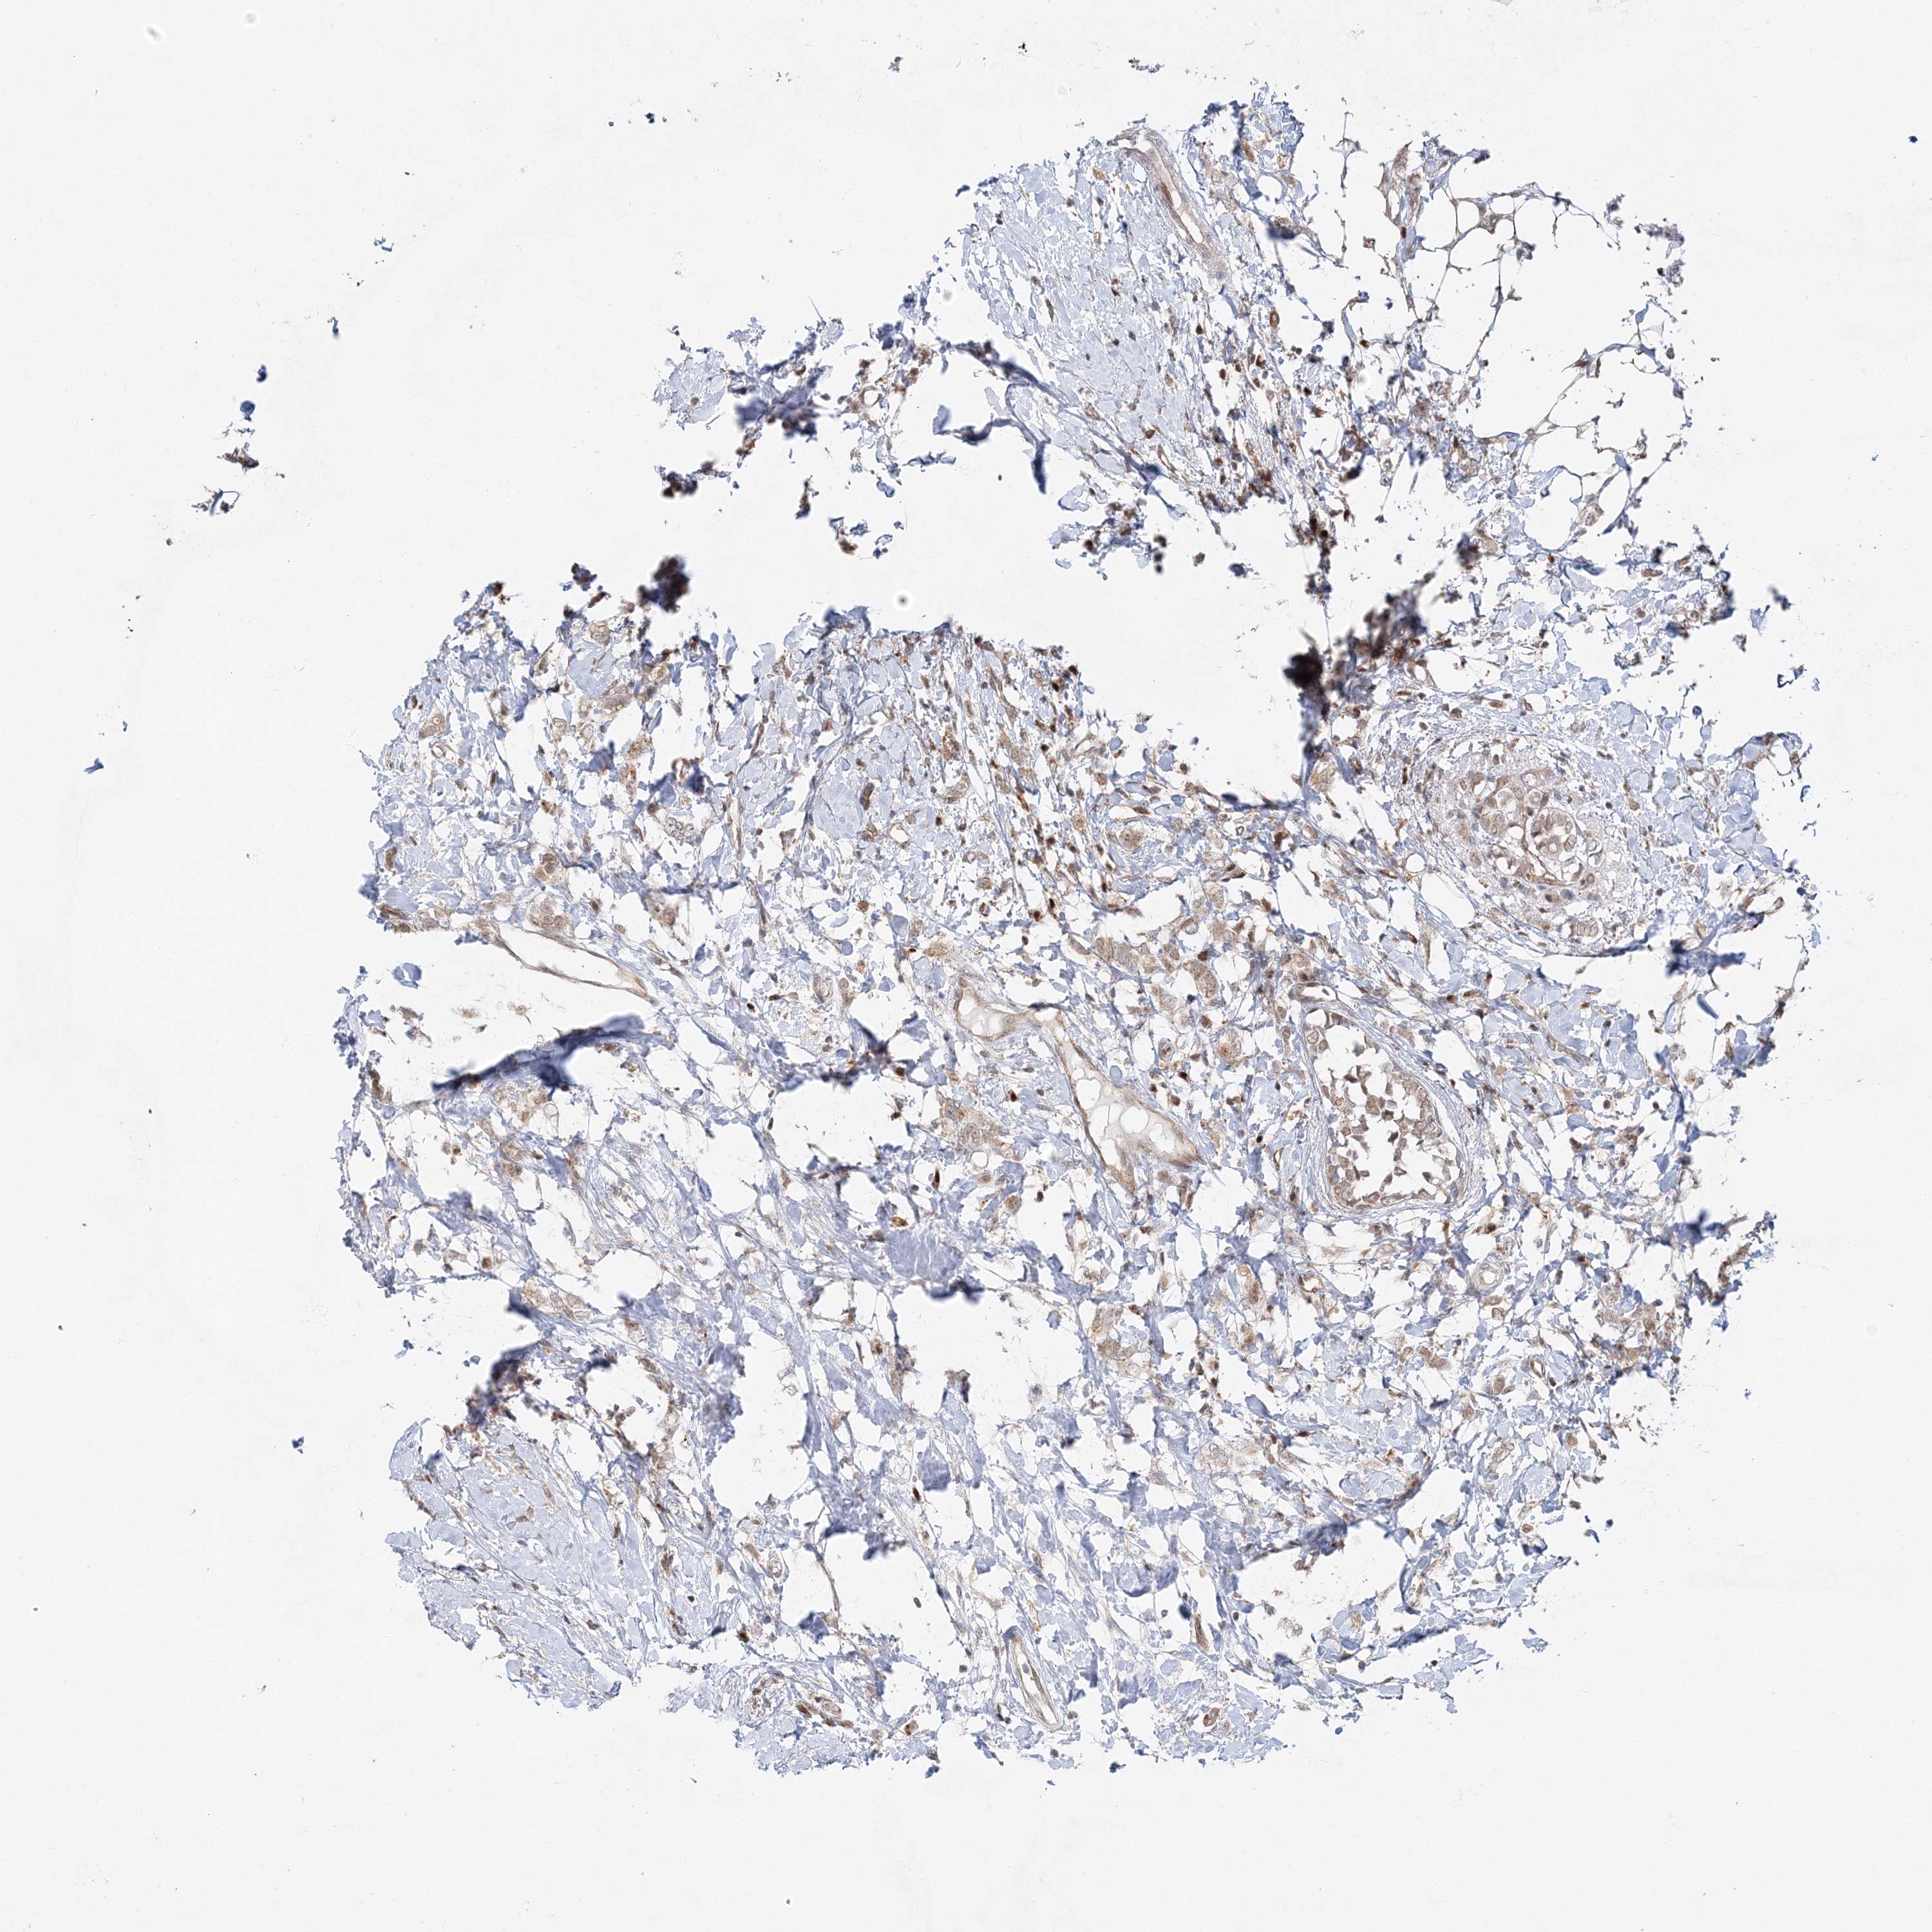

PATHOLOGY BREAST CANCER Show tissue menu

Breast cancer

Human pathology